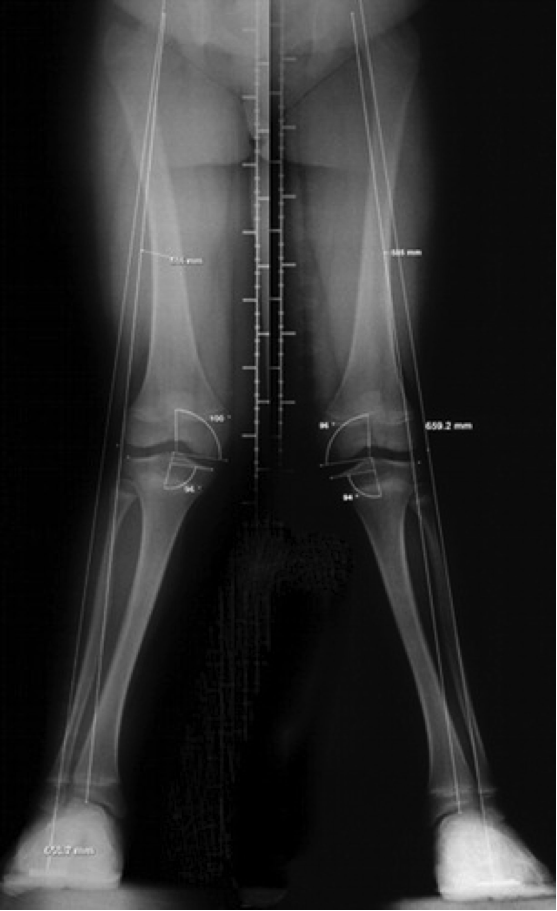

Chúng tôi đã điều trị 25 đứa trẻ liên tiếp (51 phần, 12 thủ thuật hai bên) chân chữ O và chữ X có triệu chứng bằng cách hãm sụn tăng trưởng với một nẹp tạo hình titan hai lỗ (8 nẹp; Orthofix SRL, Verona, Ý). Tất cả trẻ em được nhập vào một cơ sở dữ liệu và được xem xét như những bệnh nhân ngoại trú trong khoảng thời gian bốn tháng một lần cho đến khi việc điều trị hoàn tất (Hình 1).

Hình 1: Hình ảnh chụp cắt lớp cho thấy a) Chân chữ X hai bên và b) Chỉnh sửa sau 15 tháng điều trị bằng nẹp và vít titan ở đầu dưới xương đùi và ở đầu trên xương chày. Các phép đo chiều dài cho biết tổng chiều dài của chi (Từ trần ổ cối đến điểm đánh dấu ở gót chân) và chiều dài của trục cơ học. Các góc là góc trong đầu dưới xương đùi và góc trong đầu trên xương chày.